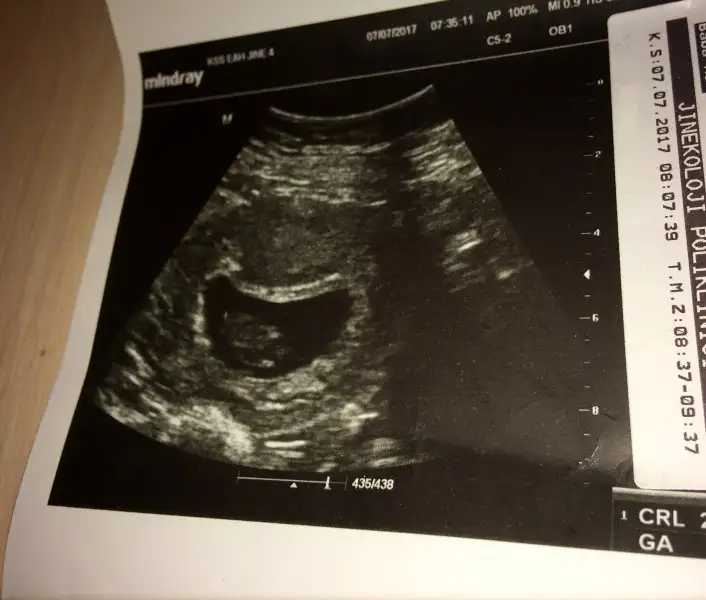

Gittim bebişimi gördüm 9+1 sata göre 9+4 ultrasona göre

Crl 24.8 çıktı

Doktor sakın söyleme midem bulanmıyo diye dedi nazar edecen diyo herşey yoşunda şimdilik çok şükür